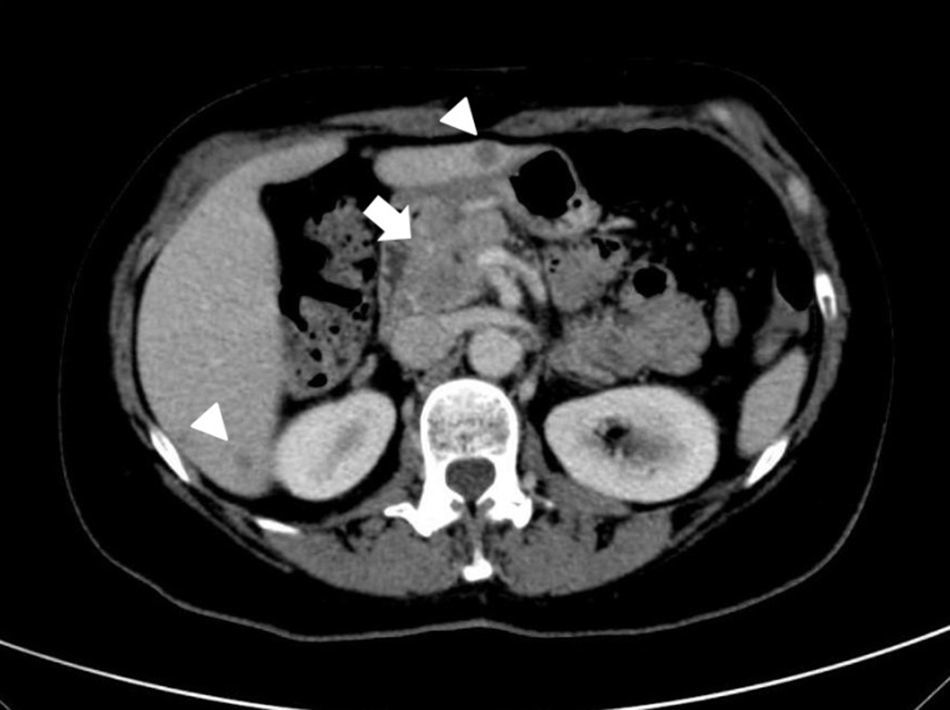

Observación clínicaMujer de 54 años que acudió al servicio de urgencias por dolor epigástrico agudo, astenia y pérdida de peso no cuantificada. Entre sus antecedentes personales destacaban: fumadora de 30 paquetes/año y consumo de alcohol de 50 gramos/semana; hipotiroidismo, y colecistectomía laparoscópica por pólipo vesicular benigno de 12mm, sin litiasis en la pieza quirúrgica. Su historia familiar únicamente incluía la muerte de un hermano por cáncer de pulmón de estirpe histológica desconocida. En la exploración física se objetivó el dolor epigástrico sin otras anormalidades. En las determinaciones de laboratorio destacaban niveles elevados de amilasa (444 U/L), lipasa (1496 U/L) y proteína C reactiva (9mg/dL), con valores normales de los marcadores tumorales a excepción de enolasa (85,5 ng/mL). La ecografía abdominal reveló una lesión focal hipoecoica en la cabeza del páncreas y múlitples lesiones focales hepáticas sugestivas de metástasis. La tomografía computarizada (TC) confirmó estos hallazgos (fig. 1). Además, mostró una lesión espiculada y heterogénea parahiliar en pulmón izquierdo sugestiva de tumor primario pulmonar (fig. 2). En la ecoendoscopia se visualizaron tres lesiones hipoecoicas de 12,5-14,5mm en la cabeza del páncreas que dilataban el conducto pancreático principal (fig. 3). El estudio anatomopatológico de estas lesiones sugirió metastasis de un carcinoma microcítico de origen pulmonar. La broncoscopia reveló una lesión en la carina que se extendía al bronquio principal izquierdo cuyo análisis histológico confirmó el diagnóstico de presunción de un carcinoma tipo oat-cell pulmonar (fig. 4). El episodio de pancreatitis aguda fue manejado de forma conservadora con buena evolución. Posteriormente, la paciente recibió quimioterapia. El seguimiento se mantuvo meses hasta que la paciente falleció.

La TC es la prueba diagnóstica más apropiada y accesible para evaluar el páncreas12. Con estas técnicas se pueden detectar lesiones focales pancreáticas que sugieran el origen maligno del episodio de pancreatitis aguda. Sin embargo, el estudio histopatológico de las lesiones pancreáticas es necesario para distinguir el origen primario versus metastásico. La mala situación clínica de estos pacientes condiciona a menudo dificultades para realizar pruebas diagnósticas invasivas, por lo que es frecuente no disponer de confirmación anatomopatológica13.